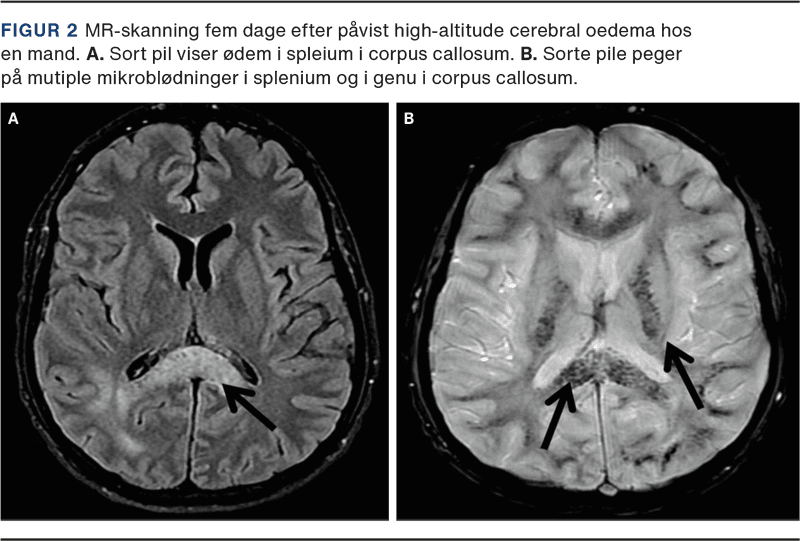

Da HACE muligvis at være en videreudvikling af svær AMS, har de to tilstande til dels den samme patogenese. Man ved ikke, hvorfor nogle patienter med AMS remitterer, og andre udvikler HACE. Individuel disposition og tilbøjelighed til HACE spiller muligvis en afgørende rolle. Ved MR-skanning har man fundet vasogent ødem, især i splenium i corpus callosum (Figur 2) [5]. Dette stemmer overens med de symptomer, som skade på splenium giver [10]. Vasogent ødem kan bekræftes måneder efter remission, hvor man har fundet hæmosiderin, et udtryk for en utæt af blod-hjerne-barriere (Figur 2). Ikke sjældent har man, ved obduktion eller røntgenundersøgelse af thorax, fundet lungeødem. Disse patienter har således haft både HACE og HAPE [4].